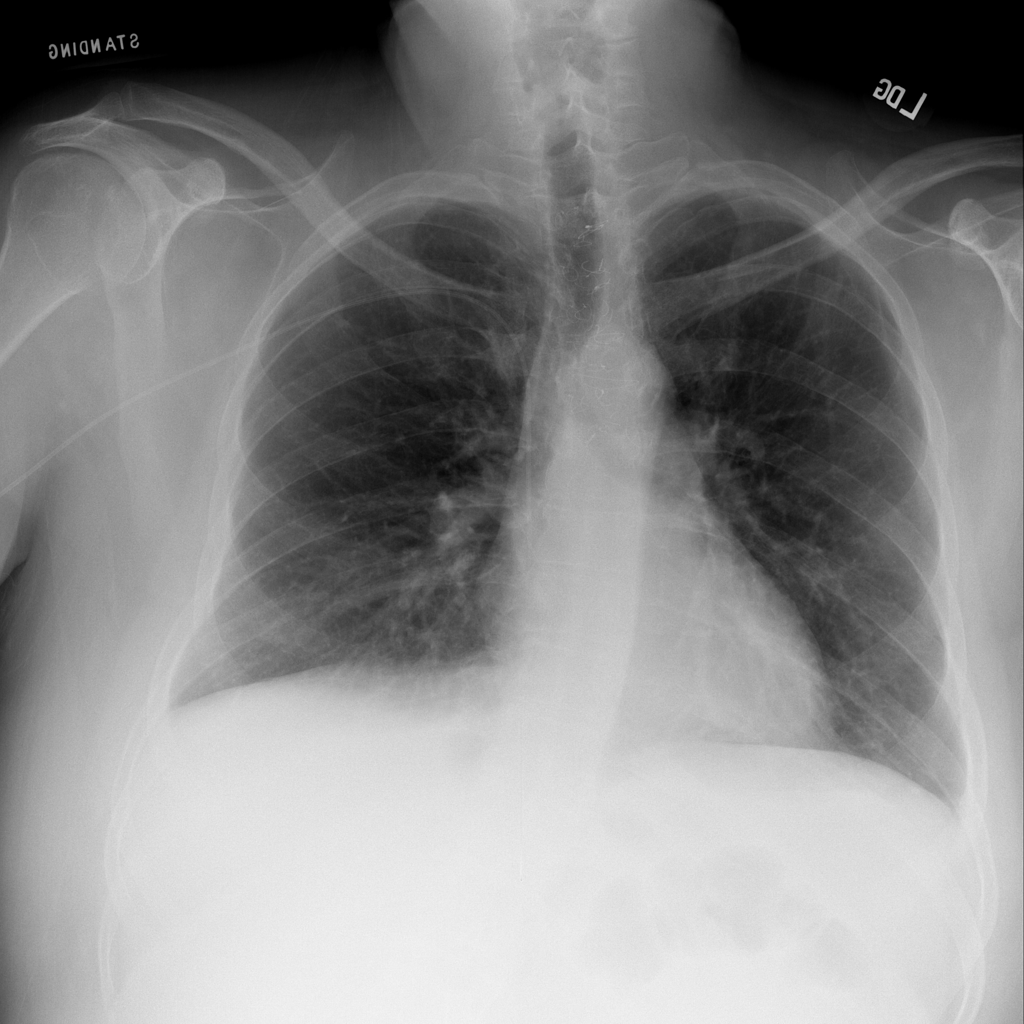

PAT-86C8 · IMG-000Effusion

PAT-86C8 · IMG-000

PA